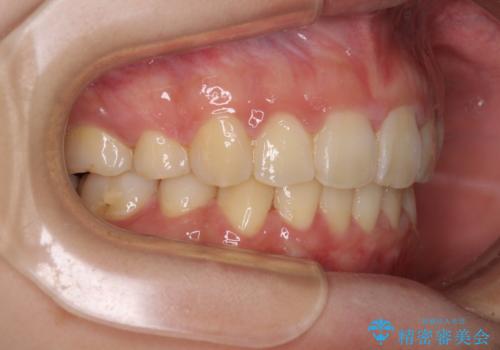

上下左右第一小臼歯4本を抜歯して、積極的に口元を引っ込めるよう、ワイヤー装置にて矯正治療を行うこととしました。

治療後には口が閉じやすくなり、患者様には大変満足していただきました。